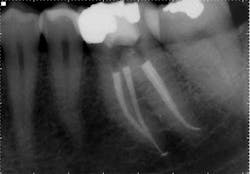

These are my least favorite teeth to treat. Most are heavily restored and the mesial-distal dimension is very small, resulting in no margin for error when locating the pulp chamber. Additionally, there can be significant inclination between the crown and root, and many will have two canals or branching at some level of the canal. (12,15) This lingual inclination of the root results in difficulty obtaining straight-line access into the buccal canal and makes locating the lingual canal almost impossible in some cases, especially if the lingual shelf of dentin is prominent. (Figure 2) Straight-line access into some lingual canals would need to be established through the mid-facial, and this is not a reasonable option for teeth restored with full-coverage crowns. (16)

have two canals. The second canal is lingual

to the main canal, and it is not uncommon for

the two canals to join at the apex. Tooth

No. 24 has a necrotic pulp and based on

the anatomy of teeth Nos. 23 and 26, a

second canal in tooth No. 24 should be expected.